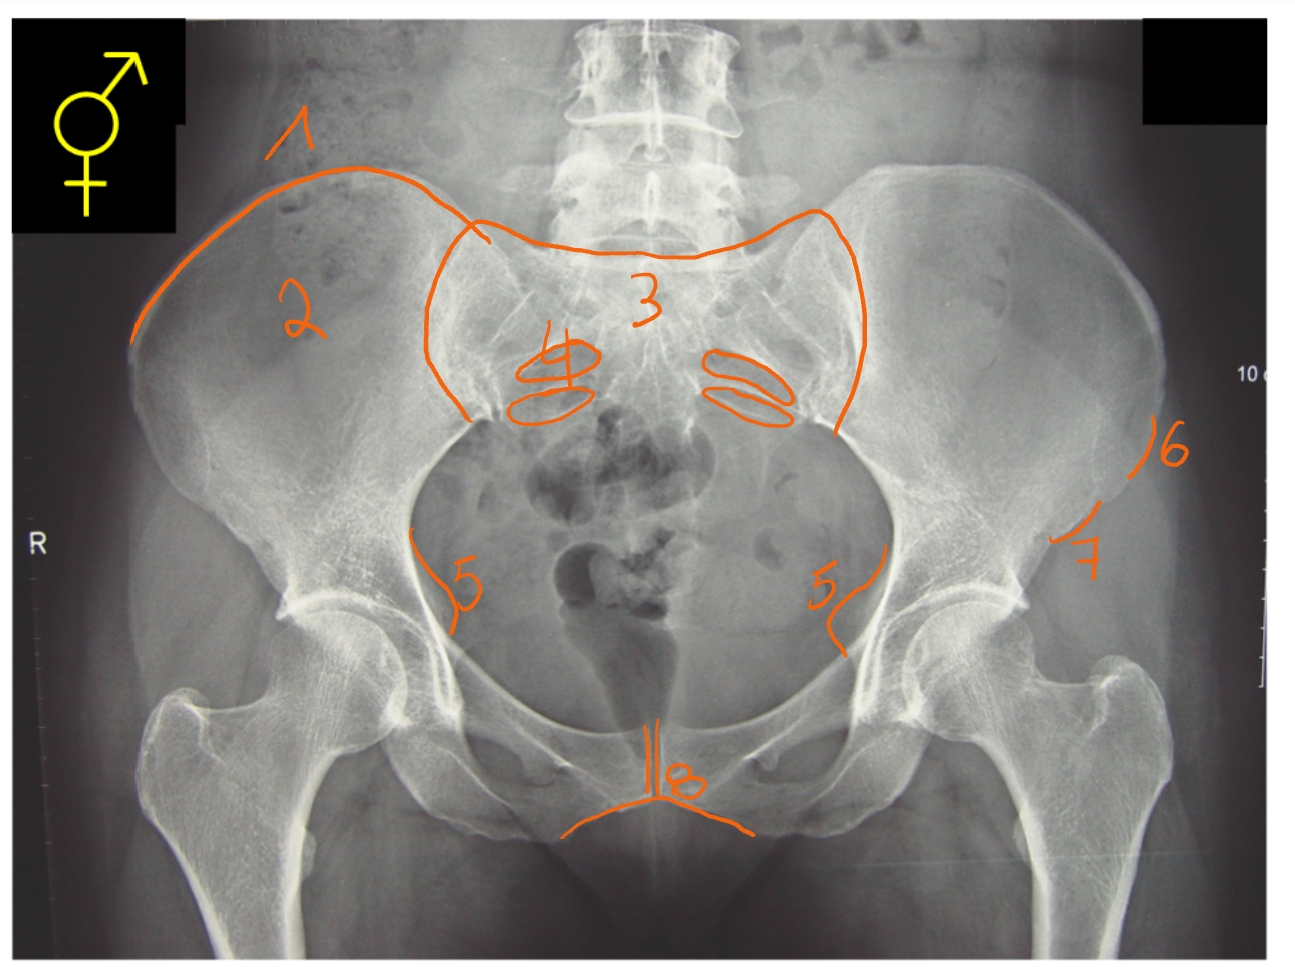

acetabulum

fovea capitis femoris

ligamentum capitis femoris ligt hierop vast

trochanter major

apofyse

caput femoris

ramus inferior

ramus superior

tuber ischiadicum

trochanter minor

pees van de m. iliopsoas ligt hierop

collum femoris

foramen obturatorium

→ rechter heup

crista iliaca

ala ossis ilii

sacrum

foramen sacrale anterius

spina ischiadica

spina iliaca anterior superior

spina iliaca anterior inferior

symfyse

→ heupgewricht van een vrouw:

ala van het os ilium is breder

gat tussen de 2 heupbeenderen is groter en breder

symfyse: stompe hoek

man of vrouw?

man

ala ossis ilii: veel hoger en smaller

gat tussen de 2 heupbeenderen: veel kleiner

symfyse: scherpe hoek